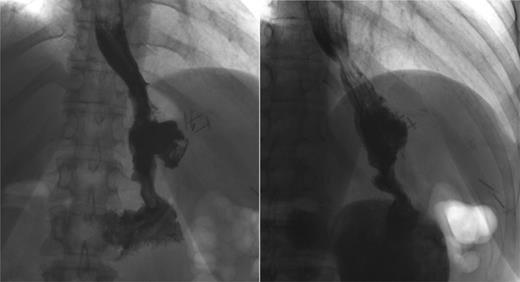

In December, the patient presented with abdominal pain and a palpable left upper quadrant mass. CT showed extravasation of oral contrast from the proximal site of the gastric sleeve in communication with a sub-left diaphragmatic collection (Fig. 4).

Recurrence. Computed tomography scan with oral contrast demonstrating a persistent small leak (arrow) 3 weeks after a negative GS.

After a multicentre complex benign oesophago-gastric multidisciplinary team (MDT) discussion, indication for a total gastrectomy was given. On 12 January 2015, patient underwent a laparoscopic completion of gastrectomy and Roux-en-Y oesophago-jejunostomy (Fig. 5). GS a week later showed no leak. The patient recovered well with no complication. At last follow-up, she remained well.

Roux-en-Y reconstruction. Laparoscopic total gastrectomy performed 5 years after the sleeve gastrectomy. Oesophago-jejunal anastomosis is indicated by the arrow.